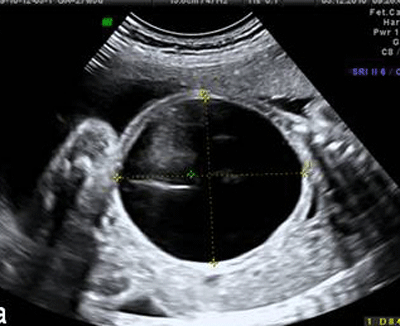

A 26-year-old pregnant woman was referred to our prenatal center for a fetal abdominal cystic mass with severe oligohydramnios detected at 27th week of gestation. Prenatal scan showed a single male fetus with a cystic avascular mass (74×84 mm) located in the left hemi abdomen pushing left hemi diaphragm (Fig. 1).

| Figure 1: A huge cyst in fetus compressing surrounding structures | |